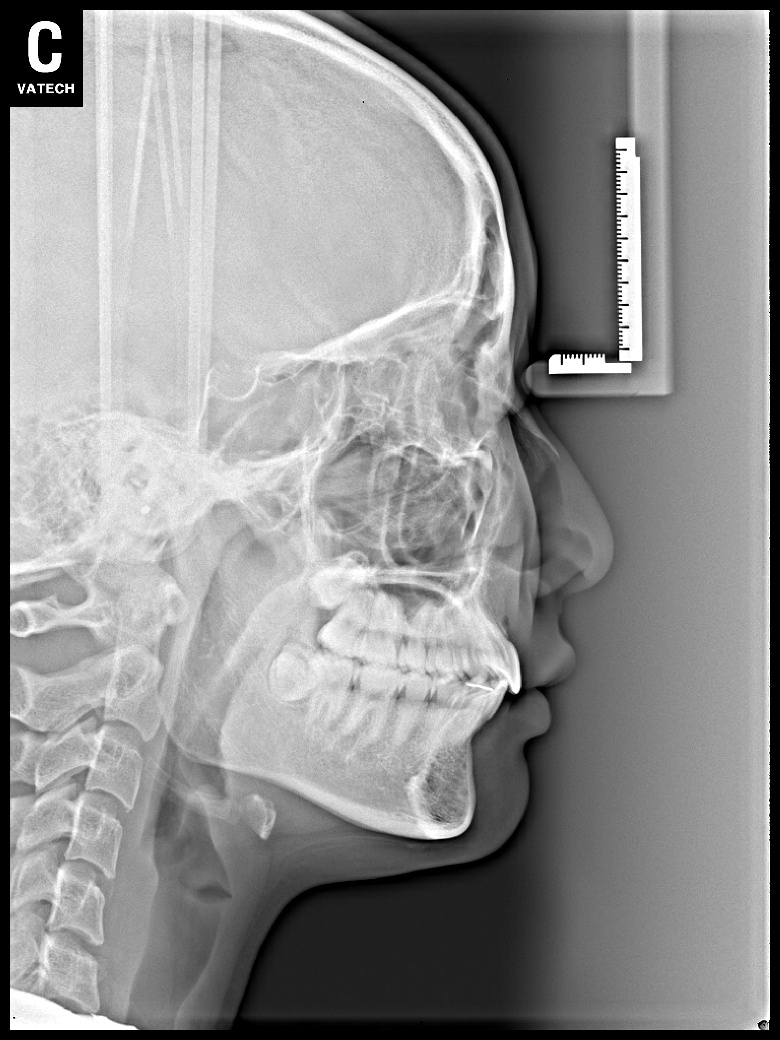

치료 후 사진입니다.